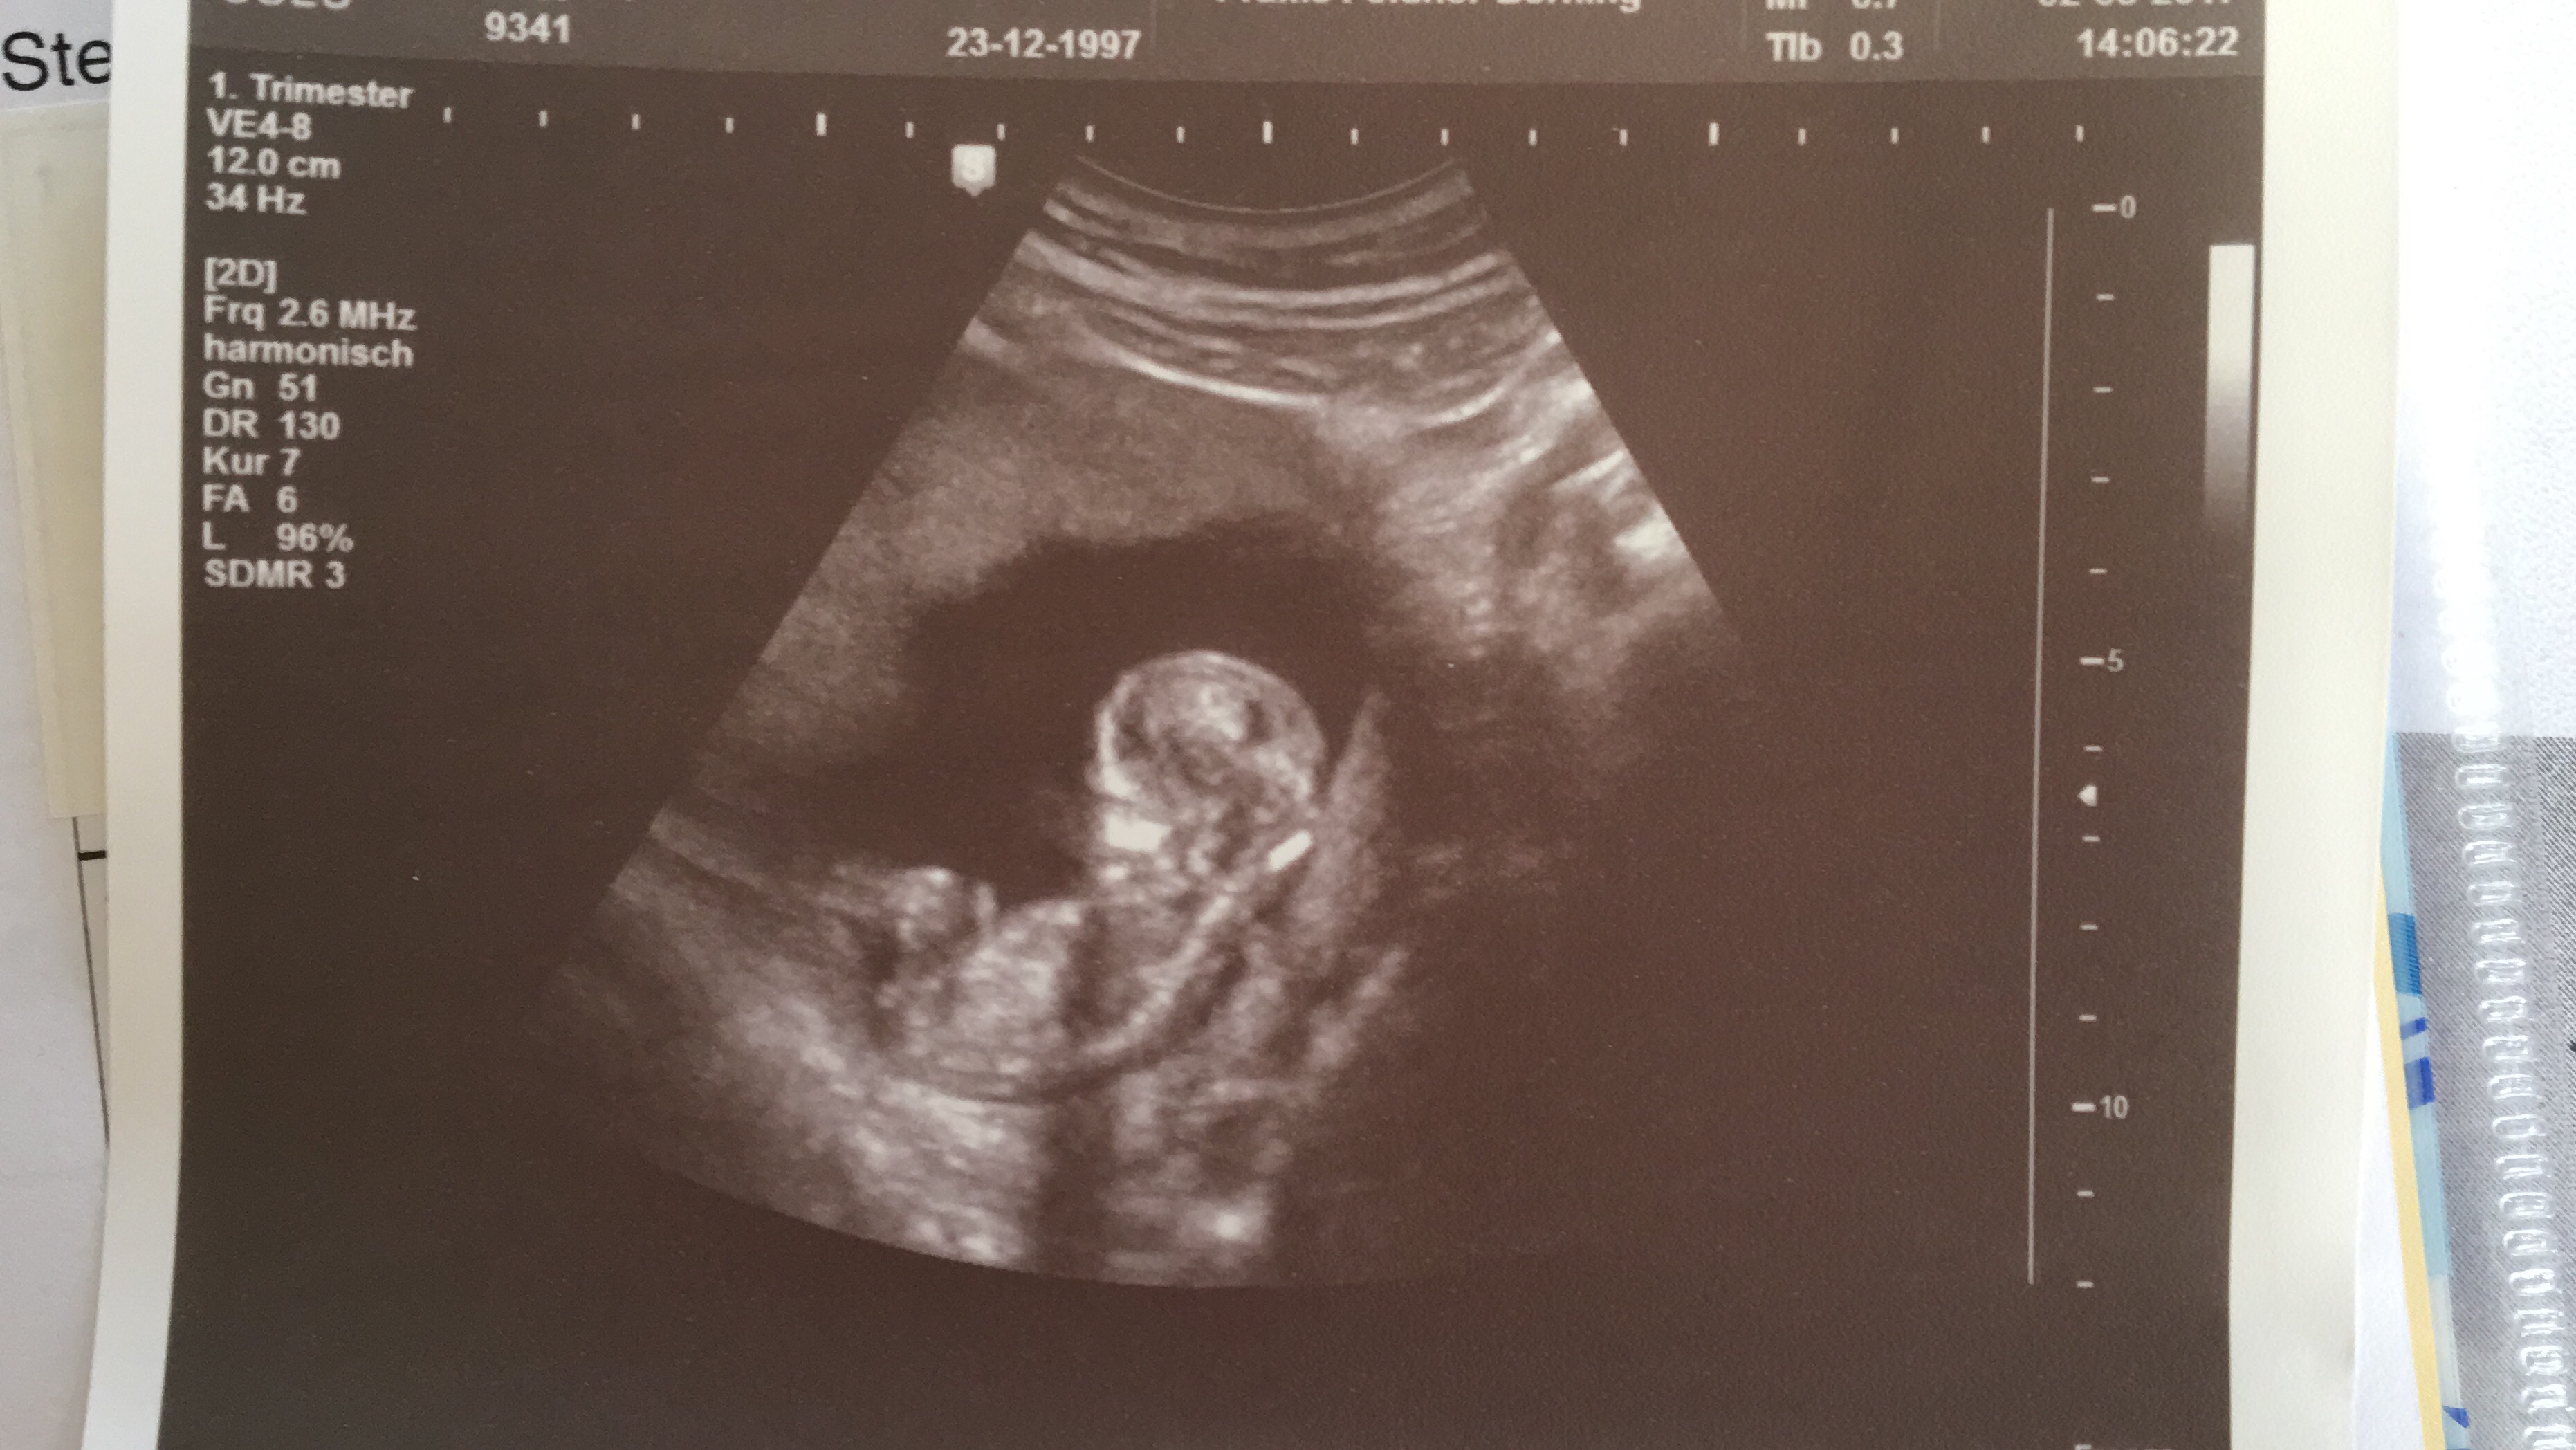

Hallo Heute (Anfang 14SSW) war ich beim Ultraschall und habe wieder ein super schönes Bild bekommen!.

Ultraschall Das SSW 5 SSW 6 SSW 7 SSW 8 SSW 9 SSW 10 SSW 11 SSW 12 SSW 13 SSW 14 SSW 15 SSW 16 SSW 17 SSW 18 SSW 19. 15 SSW Geschlecht = Mädchen oder Junge Hallo ich bin in der 15 SSW und wahr heute beim Arzt, wegen dem Geschlecht, vor 3 Wochen hat der Arzt gesagt, es könnte ein Junge werden, weil es so aussah Jetzt heute hat der Arzt gesagt, das es wahrscheinlich ein Mädchen wird, weil man 2 Streifen (laut dem Arzt Scharmlippen) gesehen hat. In der 15 SSW bewegt Ihr Baby nun regelmäßig seine Arme, Beine und den Rest der Körpermuskulatur Der kleine Fetus kann sogar an seinem Daumen saugen Lesen Sie mehr über Sie und die Entwicklung Ihres Babys nach 15 Wochen.